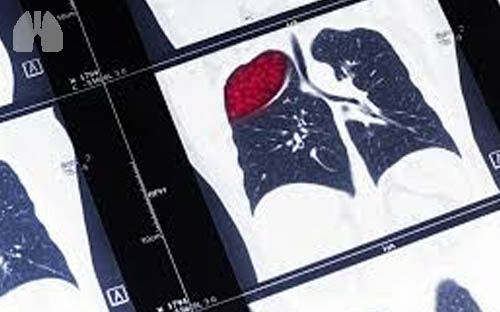

Ketika sudah mengeras, granuloma akan lebih mudah dideteksi melalui tes pengambilan gambar, seperti rontgen atau CT scan.

Bahkan, seseorang biasanya baru menyadari dirinya memiliki granuloma di paru-paru ketika dokter tak sengaja menemukannya melalui rontgen atau CT scan dada untuk pemeriksaan kondisi medis lain.

Misalnya, Anda sedang menjalani rontgen dada atau CT scan untuk memeriksa penyakit pernapasan lain, kemudian dokter menemukan titik-titik kecil di paru-paru Anda.

Setelah diidentifikasi, ternyata titik-titik tersebut merupakan granuloma.

Jika granuloma berukuran sedikit lebih besar, dokter akan memastikannya dengan positron emission tomography (PET) scan.

Scan ini dapat mendeteksi apakah granuloma tersebut berpotensi kanker atau tidak.